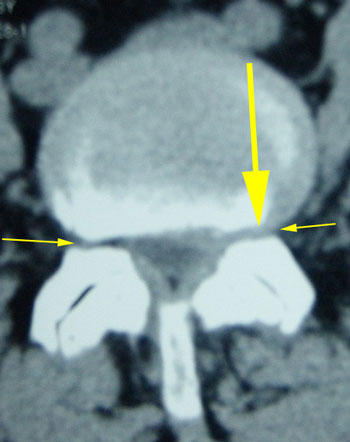

CT was ordered and shown Spinal Canal Stenosis at L4 5, and a left-sided disc prolapse with impingement of the left L4 root.

IMAGING